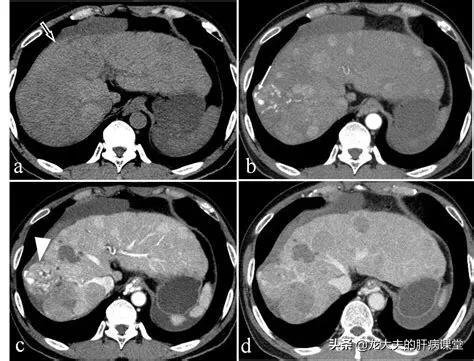

CT検査の結果が不明確な患者の中には、特に肝臓に異常が認められる場合がある。著しい結節様変化がある場合磁気共鳴検査は、異型過形成結節と肝細胞癌を区別できるので、より有益であろう。

この中年男性は慢性B型肝炎の既往があり、超音波検査で肝右葉下節に不均一な低エコーを認め、臨床検査でα-フェト蛋白の上昇を認め、さらに磁気共鳴検査で古典的な丸みを帯びた低信号域を認め、増強検査で不均一な増強を認めたことから、小さな肝細胞癌であることが明らかになり、3年近く手術を受けていた。

また、典型的な病変であれば、強調CTで診断を確定することができますが、小さな肝臓がんの中には、やっかいで非典型的なものもあり、特殊な造影剤を用いたMRIによる強調検査が必要になることがあります。